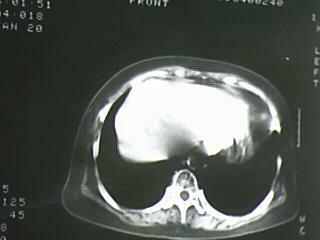

以下是引用bmw011在2009-4-14 19:14:00的发言:[br]右肺继发型肺结核---纵隔淋巴结多发钙化----左肺支扩。支持

以下是引用杀毒软件在2009-4-14 17:52:00的发言:[br]考虑---右肺继发型肺结核---纵隔淋巴结多发钙化----左肺支扩

以下是引用黑白光影在2009-4-14 20:36:00的发言:[br]右肺继发型肺结核;左下慢性支气管炎性病变。